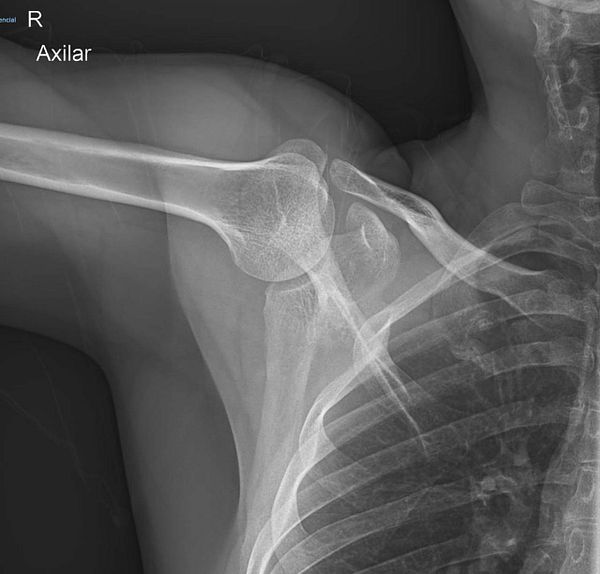

See x-ray photos of right shoulder #life